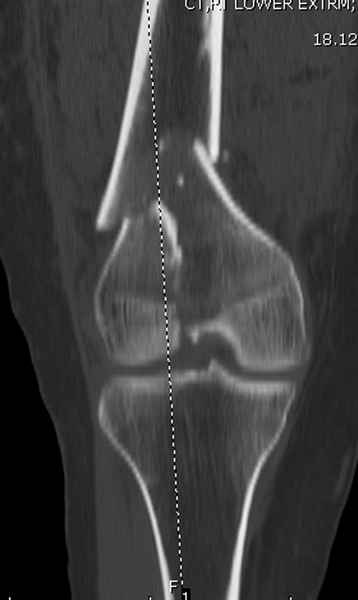

При наличии различных имплантов, любые варианты: слева (полу) открытым - мининвазивным, а справа закрытым интрамедуллярным методом, его считаем более чем приемлемым для фиксации данных переломов.

Проксимальная и дистальная блокировка, независимо от техники введения штифта, ретроградно или антеградно, гарантирует сращение сегментарных переломов бедра без укорочения. Штифты диаметром 12 мм с блокировкой сверху и вниз двумя шурупами выдерживают вес 75 кг больного, что позволяет раннюю профилактику контрактур.

Погоня за "красивой рентгенограммой" не всегда оправдана для фиксации кости, где имеется массивное мягкотканое покрытие. Если так уж хочется исправить положение кости, то при наличии ЭОП, большие костные фрагменты могут быть развернуты или приближены к основному фрагменту методом применения Joystick.

Из-за вариабельности установки дистальных шурупов и возможности перкутанного введения проксимально предпочитаем DePuy Polyax, хотя на сегодняшнем маркете множеств вариантов фиксации дистального бедра перкутанном методом.